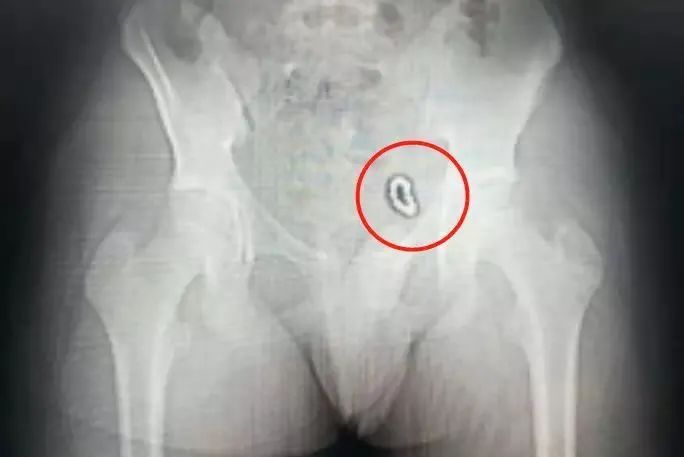

拍完X光片后,医生发现:

浩浩下腹部左侧像是挂了一道环形“手串”,10多颗珠子紧紧连在一起,固定在膀胱左侧壁。

尿检后发现,浩浩已经有了慢性膀胱炎,细菌正在尿液中滋长。

好在经过手术,医生终于把这“巴克球”取出来。